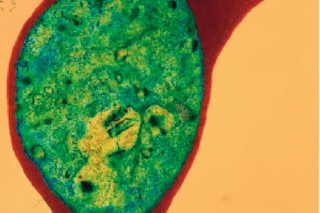

The red blob in this picture is a human red blood cell, and the green blob in the middle of it is a pack of the malaria-causing parasites Plasmodium falciparum. Other species of the single-celled Plasmodium can give you malaria, but if you're looking for a real knock-down punch, P. falciparum is the parasite for you. It alone is responsible for almost all of the million-plus deaths due to malaria.